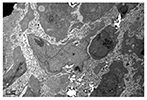

瘤细胞体积大,胞质丰富,瘤细胞表面大量微绒毛,微绒毛长短不一,粗细较均匀,少数有分枝(图2)。胞质电子密度低,细胞器有线粒体、多聚核糖体、粗内质网及发达的高尔基复合体。核大,核不规则,部分有深的切迹,染色体少而分散。未见桥粒有其他细胞间连接,细胞外无基底膜。

标本送中山大学中山医学院电镜室。取新鲜组织用2.5%戊二醛和1%锇酸双固定后按常规脱水、浸透,Epon.618包埋,超薄切片经醋酸铀-枸橼酸铅染色,Philip-TECNAI10型透射电子显微镜观察。